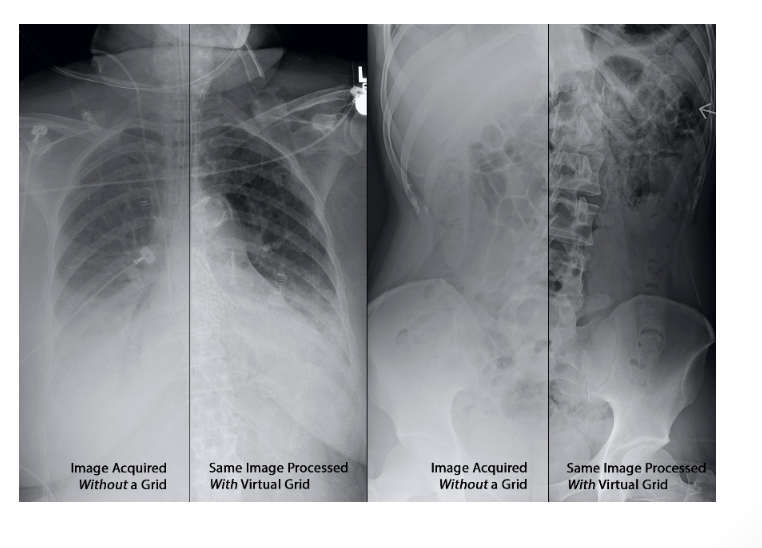

What is the objective of using Grids in radiography?

To minimize the amount of scattered radiation coming from the patient before it reaches the IR.

How do Grids improve radiographic contrast?

Improves contrast by reducing the amount of scattered radiation reaching the IR.

Absorbs scatter radiation which improves visibility of detail